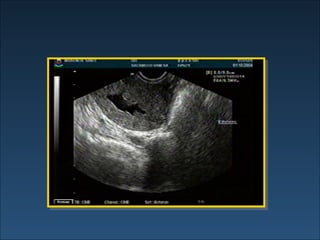

INFERTILIDAD - Evaluación Factor Uterino  : Ecografía HSG Ecosonografía Histeroscopía Factor tubario : HSG

Histerosonografía

INFERTILIDAD - EvaluaciónFactor Uterino : Ecografía HSG Ecosonografía Histeroscopía Factor tubario : HSG